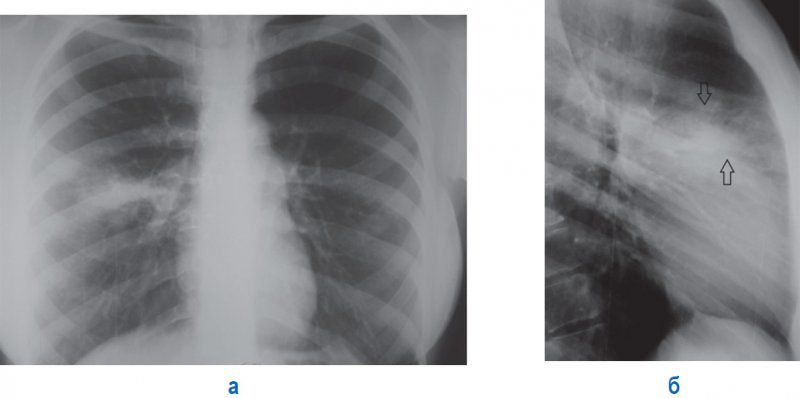

Левосторонняя пневмония нижней доли легкого

Рисунок 10. Левосторонняя пневмония нижней доли легкого. А – рентгенограмма в прямой проекции (трудно определяется инфильтрация в нижней доле слева, так как она располагается за тенью сердца). Б – рентгенограмма в левой боковой проекции (отмечается участок инфильтрации над задним скатом диафрагмы в S10 нижней доли слева)